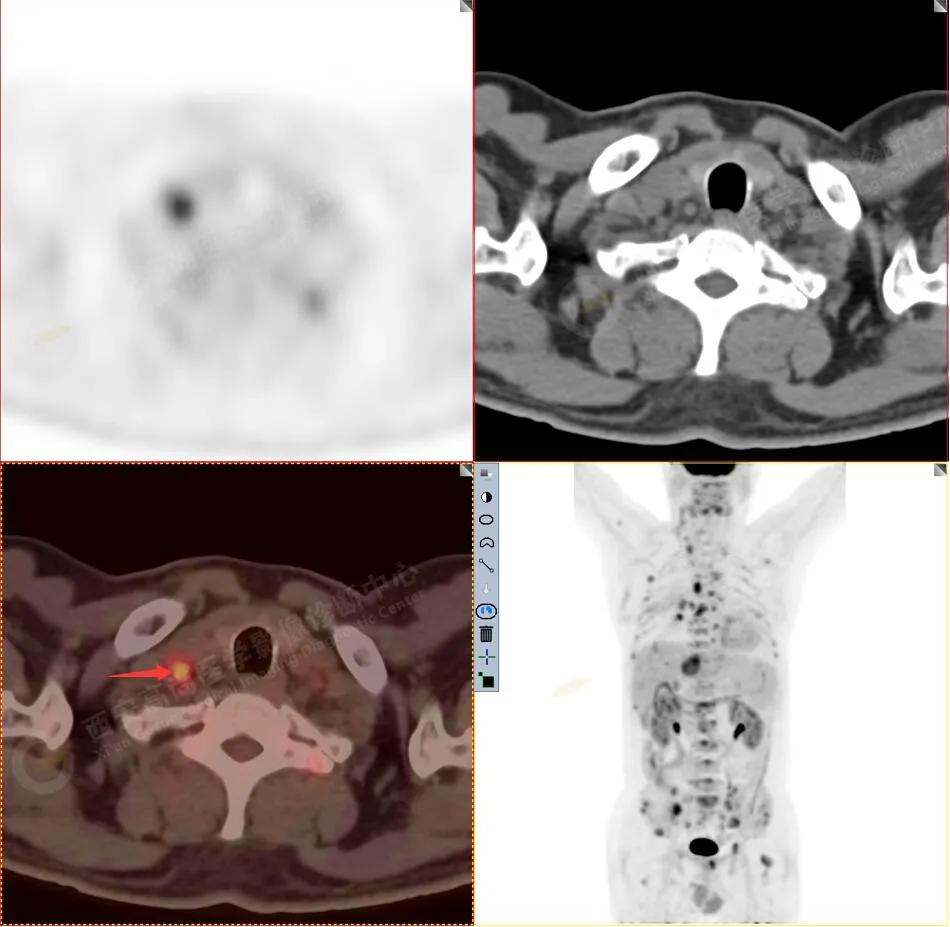

右颈部淋巴结转移

1R组淋巴结转移

右腋窝及纵隔淋巴结转移

纵隔淋巴结转移

胸骨、淋巴结转移

3.右侧颈部(Ⅱ-Ⅴ区)、右侧腋窝区、右侧肺门及纵隔(1R、1L、2、4、6、7组)、肝门区多发肿大淋巴结,呈不同程度异常增高,均考虑为淋巴结转移。